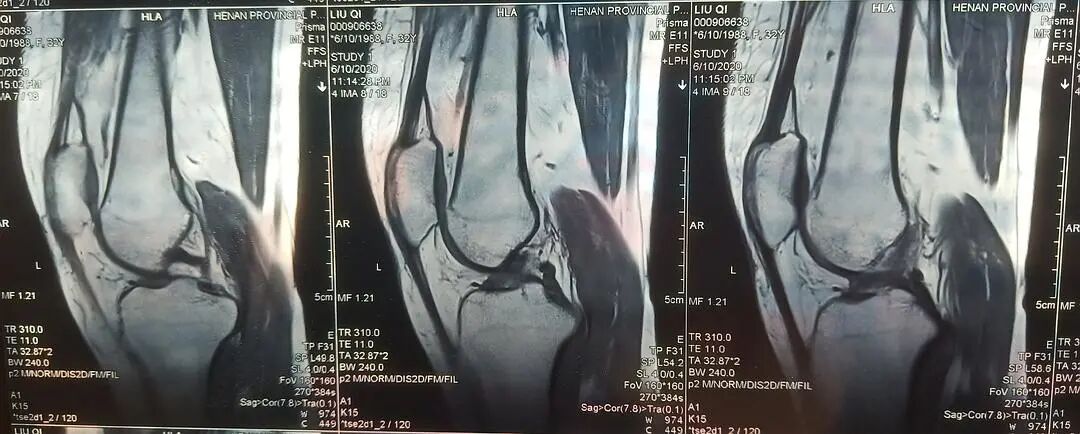

需要做的检查

临床查体、血液检查、关节液检查、X射线、CT检查、MRI检查、关节镜检查、病理检查。